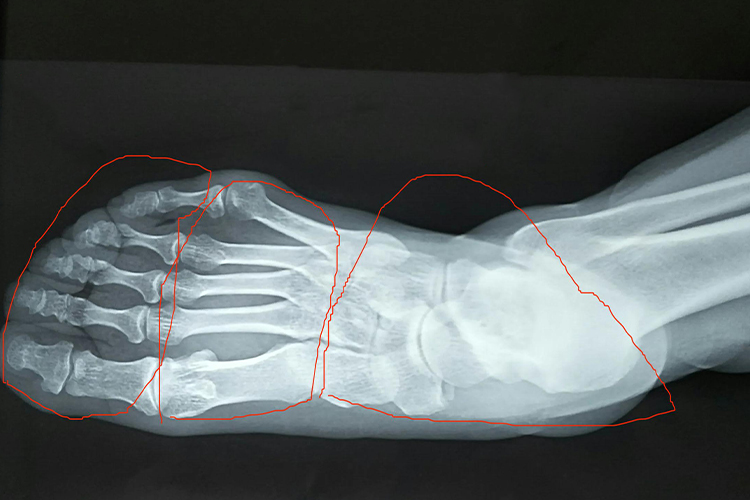

正常足部在X线影像不会有骨裂(缝隙),错位、畸形等异常情况的出现,通过X线检查,足部可分为跗骨、跖骨和趾骨,其中跗骨属于短骨,跖骨属于长骨,相当于手的掌骨,趾骨属于长骨,相当于手的指骨,比指骨短小。